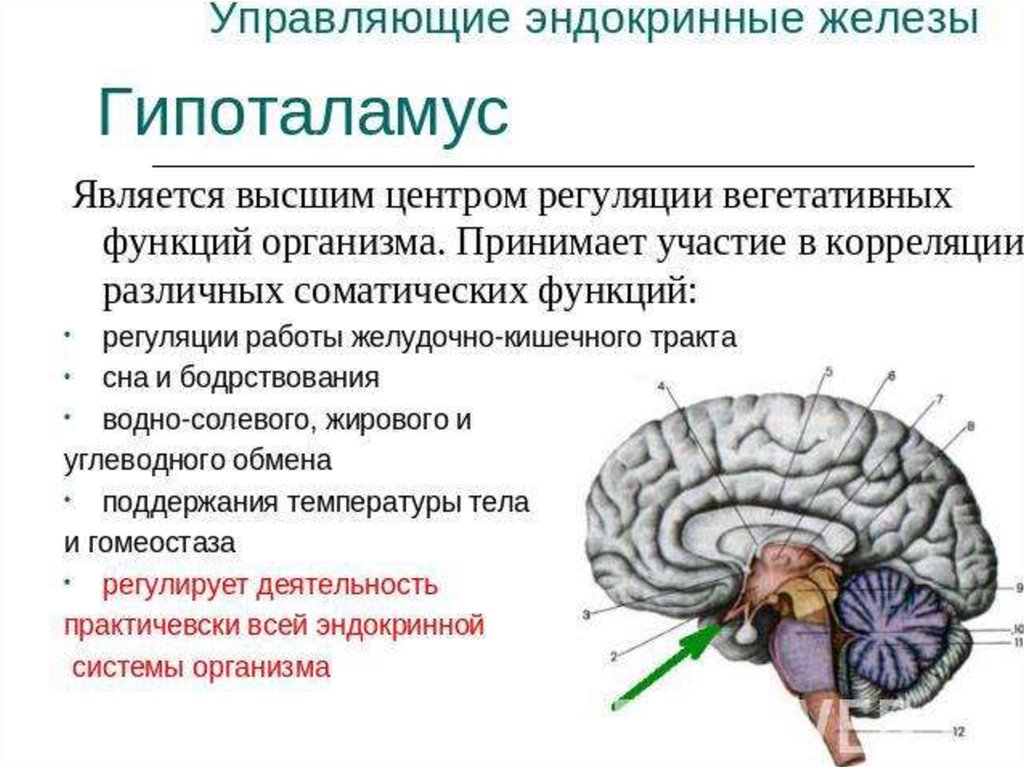

Как работает центр насыщения в гипоталамусе: визуальные иллюстрации